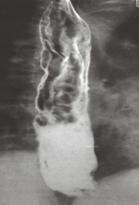

identificarea varicelor se face prin examen radiologic cu pasta groasa baritata

esogastroscopie (examenul cel mai fiabil, care stabileste si gradul evolutiv al varicelor esofagiene - clasificarea Dagradi, cea mai folosita, cuprinde 5 grade evolutive:

gradul I = varice de 1-2 mm largime si 1-2 mm elevatie fata de planul mcoasei, ce apar numai in timpul manevrei Valsalva

gradul II = varice permanente de 2-4 mm largime si 2-4 mm elevatie

gradul III = varice cu dimensiuni de 4-6 mm

gradul IV = varice de 6-8 mm

gradul V = varice care oclud complet lumenul esofagian)

splenoportagrafie (evidentiaza refluxul venos gastroesofagian); efractia varicelor esogastrice e urmata de aparitia hemoragiei digestive superioare (complicatie de temut).